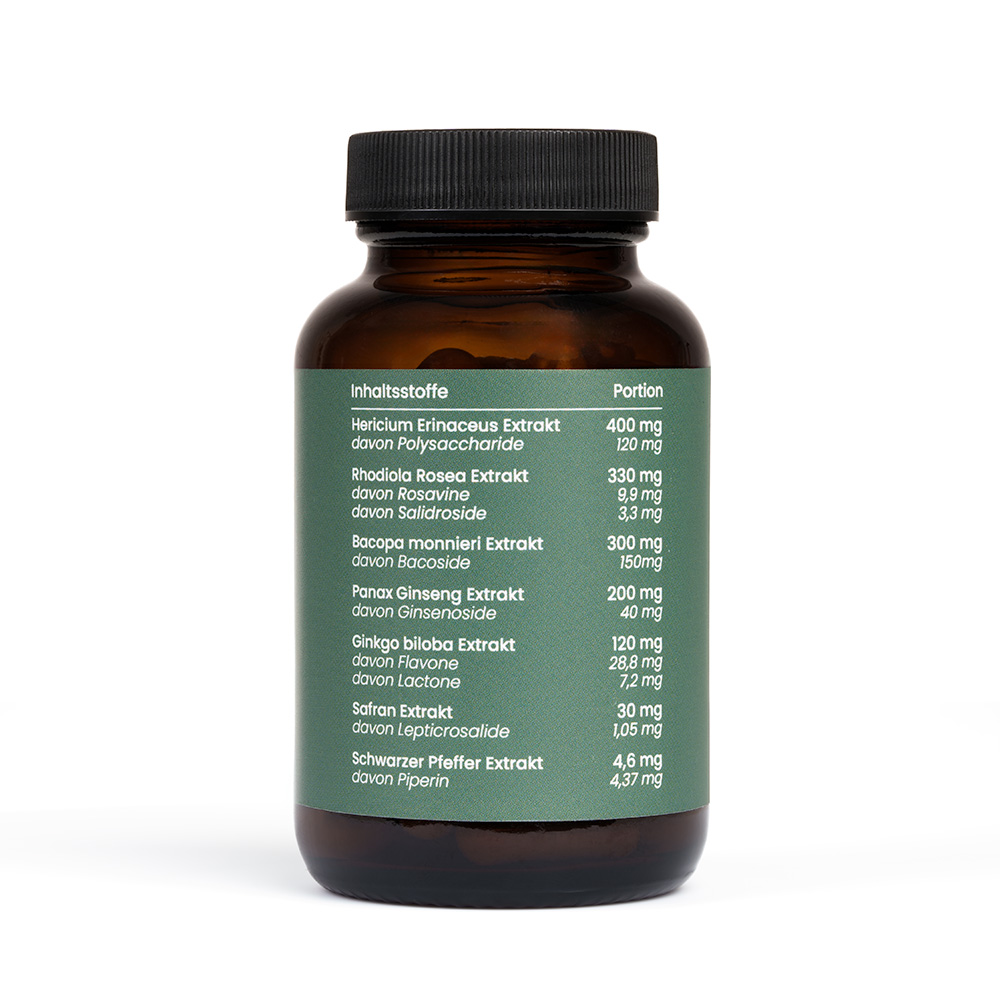

| Inhaltsstoffe | Menge pro Portion

(1 Kapsel) |

*NRV |

|---|---|---|

| Hericium Erinaceus Extrakt | 200 mg | ** |

| davon Polysaccharide | 60 mg | ** |

| Rhodiola Rosa Extrakt | 165 mg | ** |

| davon Rosavine | 4,95 mg | ** |

| davon Salidroside | 1,65 mg | ** |

| Bacopa Monnieri Extrakt | 150 mg | ** |

| davon Bacoside | 75 mg | ** |

| Panax Ginseng Extrakt | 100 mg | ** |

| davon Ginsenoside | 20 mg | ** |

| Ginkgo biloba Extrakt | 60 mg | ** |

| davon Flavone | 14,4 mg | ** |

| davon Lactone | 3,6 mg | ** |

| Safran Extrakt | 15 mg | ** |

| davon Lepticrosalide | 0,53 mg | ** |

| Schwarzer Pfeffer Extrakt | 2,3 mg | ** |

| davon Piperin | 2,19 mg | ** |

| Vitamin B5 | 3 mg | 50% * |

| Vitamin B6 | 0,7 mg | 50% * |

| Vitamin B12 | 1,25 µg | 50% * |

| Zink | 1,66 mg | 17% * |

* Nährstoffbezugswerte für die tägliche Zufuhr gemäß EU Verordnung 1169/2011

** kein NRV vorhanden